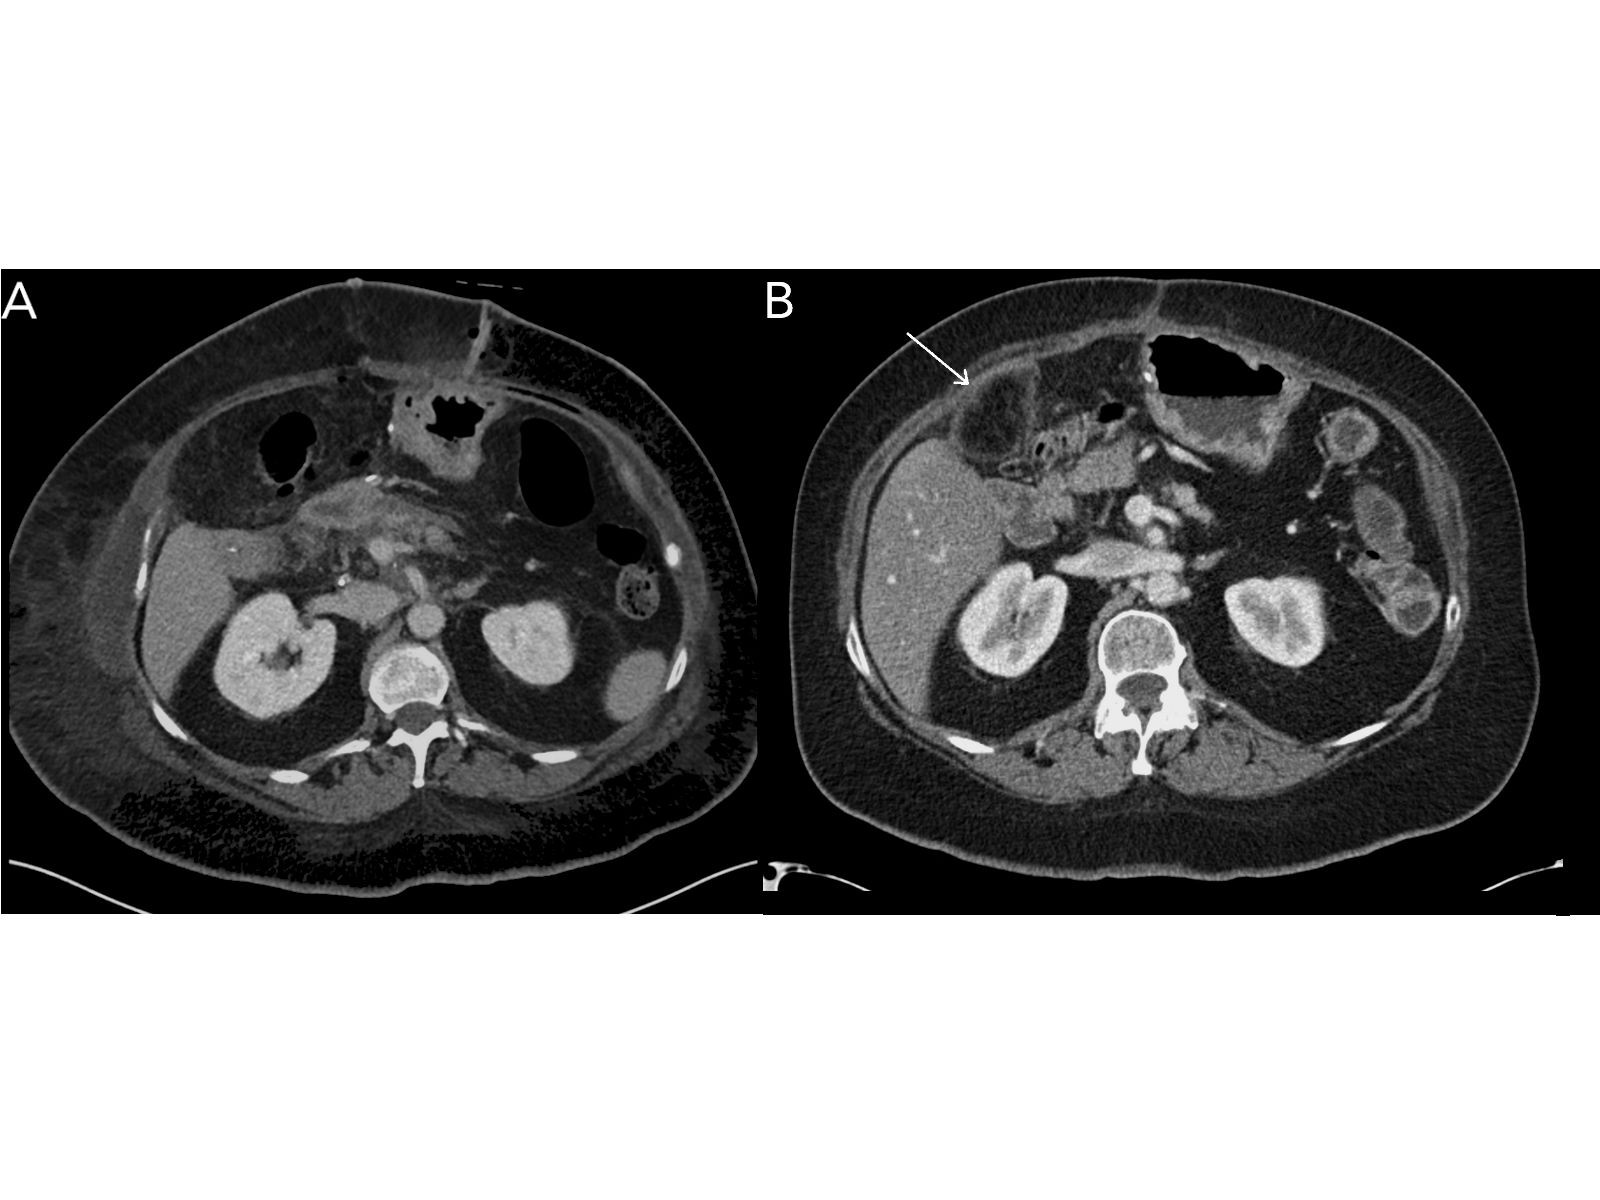

CT images from a 58-year-old female who underwent surgery for pancreatic cancer are seen below. Image A is a contrast-enhanced CT scan obtained in the immediate postoperative period. Image B is from a contrast-enhanced CT scan performed 4 months post-op. A new structure in the right upper quadrant on the postoperative CT scan is indicated by the arrow.

Based on the images shown, what is your diagnosis?